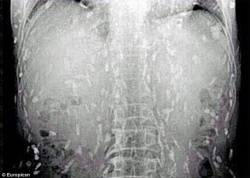

Рентген-снимки мужчины ужаснули врачей

В Китае в Гуанчжоу мужчина обратился в больницу с жалобами на сильные боли в животе и зуд кожи. После того как врачи получили рентген-снимки китайца, они ужаснулись: все тело мужчины было заражено солитером, сообщает ТСН.ua.Узнав, что пациент является большим любителем суши, врачи сделали вывод, что мужчина заразился червями-паразитами после употребления в пищу сашими. Исследования подтверждают, что употребление в пищу сырой или не достаточно хорошо доваренной рыбы может привести в результате к целому ряду паразитарных инфекций. Заражение червем-солитером возникает после попадания в организм личинок Diphyllobothrium, которые находятся в пресноводной рыбе, тем не менее, маринованной и копченой рыбы также могут содержатся личинки червей. Подобные случаи заражения все чаще встречаются в более развитых странах. Канадские врачи утверждают, что это неразрывно связано с растущей популярностью суши. Нэнси Крейг, автор исследования сделала вывод, что не только японские суши а также сашими могут стать источником заражения солитером, но и в принципе любые блюда из сырой либо маринованной рыбы. Читайте также: В Питере появился аппаратный LPG массаж Ученые: чай в пакетиках вреден для здоровья Ученые назвали самые эффективные диеты Доктор Инь из больницы в Гуанчжоу, куда попал зараженный китаец, заявил, что употребление сырой или полусырой пищи, загрязненной яйцами ленточных червей, в результате может привести к цистицеркозу, при которой взрослые черви попадают в кровь человека. В частности этот тип инфекционного заболевания является опасным для жизни человека, в том случае если он достигает головного мозга. | |

В Китае в Гуанчжоу мужчина обратился в больницу с жалобами на сильные боли в животе и зуд кожи. После того как врачи получили рентген-снимки китайца, они ужаснулись: все тело мужчины было заражено солитером, сообщает ТСН.ua.